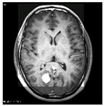

This work collects images from the Kaggle Brain MRI for Brain Tumor Detection dataset, which consists of 253 files with cancer and non-cancer brain images. The sample MRI is illustrated in Figure 2. The dataset has two folders: no tumor encoded as 0 and tumor as 1. The labeled data is more helpful in extracting the patterns from the MRI, which is used to predict the new images related output. The collected image consists of noise information that reduces the performance of brain tumor recognition accuracy. Therefore, image noise should be eliminated to improve the overall prediction efficiency.

Figure 2.

MRI samples Normal Brain MRI (Y1 to Y8) Benign tumor MRI (Y9 to Y15) Malignant tumor MRI (Y16 to Y21).